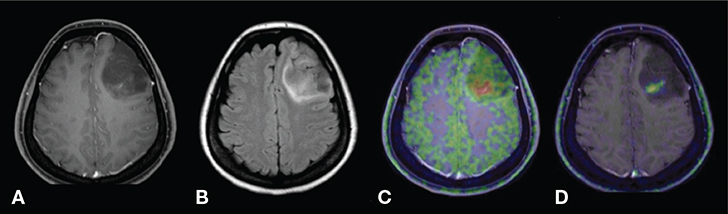

Only three agents – 18F-FGln, 11C-ACBC and 18F-FACBC – use ASCT(2) transporters. Although ASCTs are absent on endothelial cells, all three agents have shown to readily cross the BBB, probably through LAT transporters. Their main advantage over LAT-associated agents stems from the fact that ASCTs are minimally expressed in normal brain, leading to very low uptake in healthy tissues (Figure 4) (80). After entering the tumor cell, only 18F-FGln becomes incorporated into proteins; 11C-ACBC and 18F-FACBC (also called 18F-Flucoclovine), two non-natural amino acid-based agents, cannot be used in metabolic pathways and will instead be trapped in the cell (Figure 2) (29). In clinical practice, uptake of all three agents will reflect overexpression of ASCT2 (and LAT for crossing the BBB); direct evidence for increased protein synthesis however is only seen for 18F-FGln uptake (49, 52, 81, 82).

Figure 4. T1-weighted post-contrast (A), FLAIR (fluid-attenuated inversion recovery; B), 11C-MET PET (C) and 18F-FACBC PET (D) images of a patient with diffuse astrocytoma, WHO grade II, IDH mutated. The conventional MR images show a poorly enhancing lesion with some high signal surrounding the lesion. Although increased PET agent uptake can be seen in a small part of the tumor on both the 11C-MET and 18F-FACBC PET images, this case also illustrates the relatively high uptake of the natural amino acid-based 11C-MET in the healthy brain parenchyma compared to the unnatural amino-acid based 18F-FACBC which can result in decreased T/N ratios. This figure is reproduced – with new figure legend appropriate for current book chapter – from Tsuyuguchi et al. (2017), Figure 1 Case 1, under the terms of the Creative Commons Attribution License (http://creativecommons.org/licenses/by/3.0) (80).